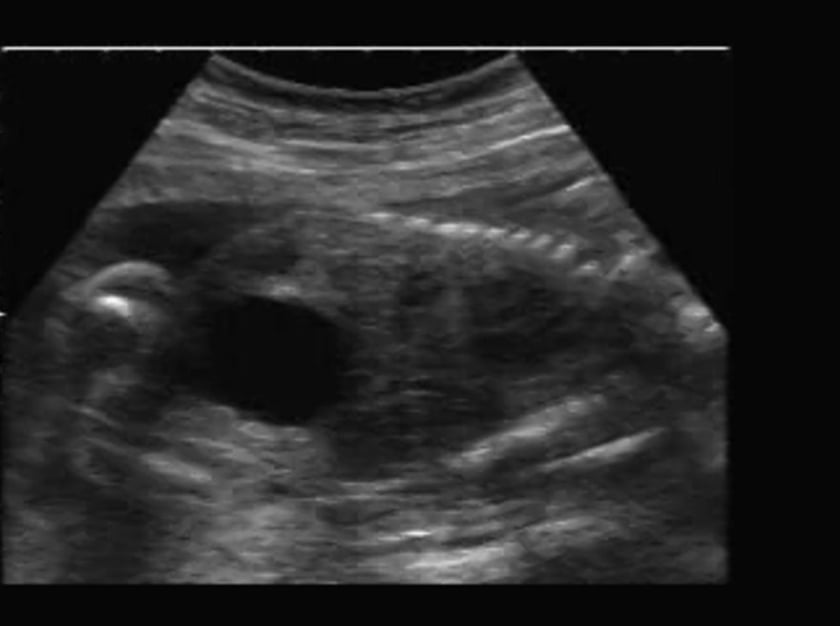

From www.researchgate.net

Fetal posterior urethral valve (PUV). a Sagittal US image of the Male Posterior Urethral Valve Posterior urethral valves (puv) are obstructive membranes that develop in the urethra (tube that drains urine from the bladder), close to the bladder. Posterior urethral valves are a rare congenital disorder affecting the male urinary tract,. What are posterior urethral valves? The valve can obstruct or block the outflow of. Posterior urethral valves are obstructing flaps of tissue in the. Male Posterior Urethral Valve.